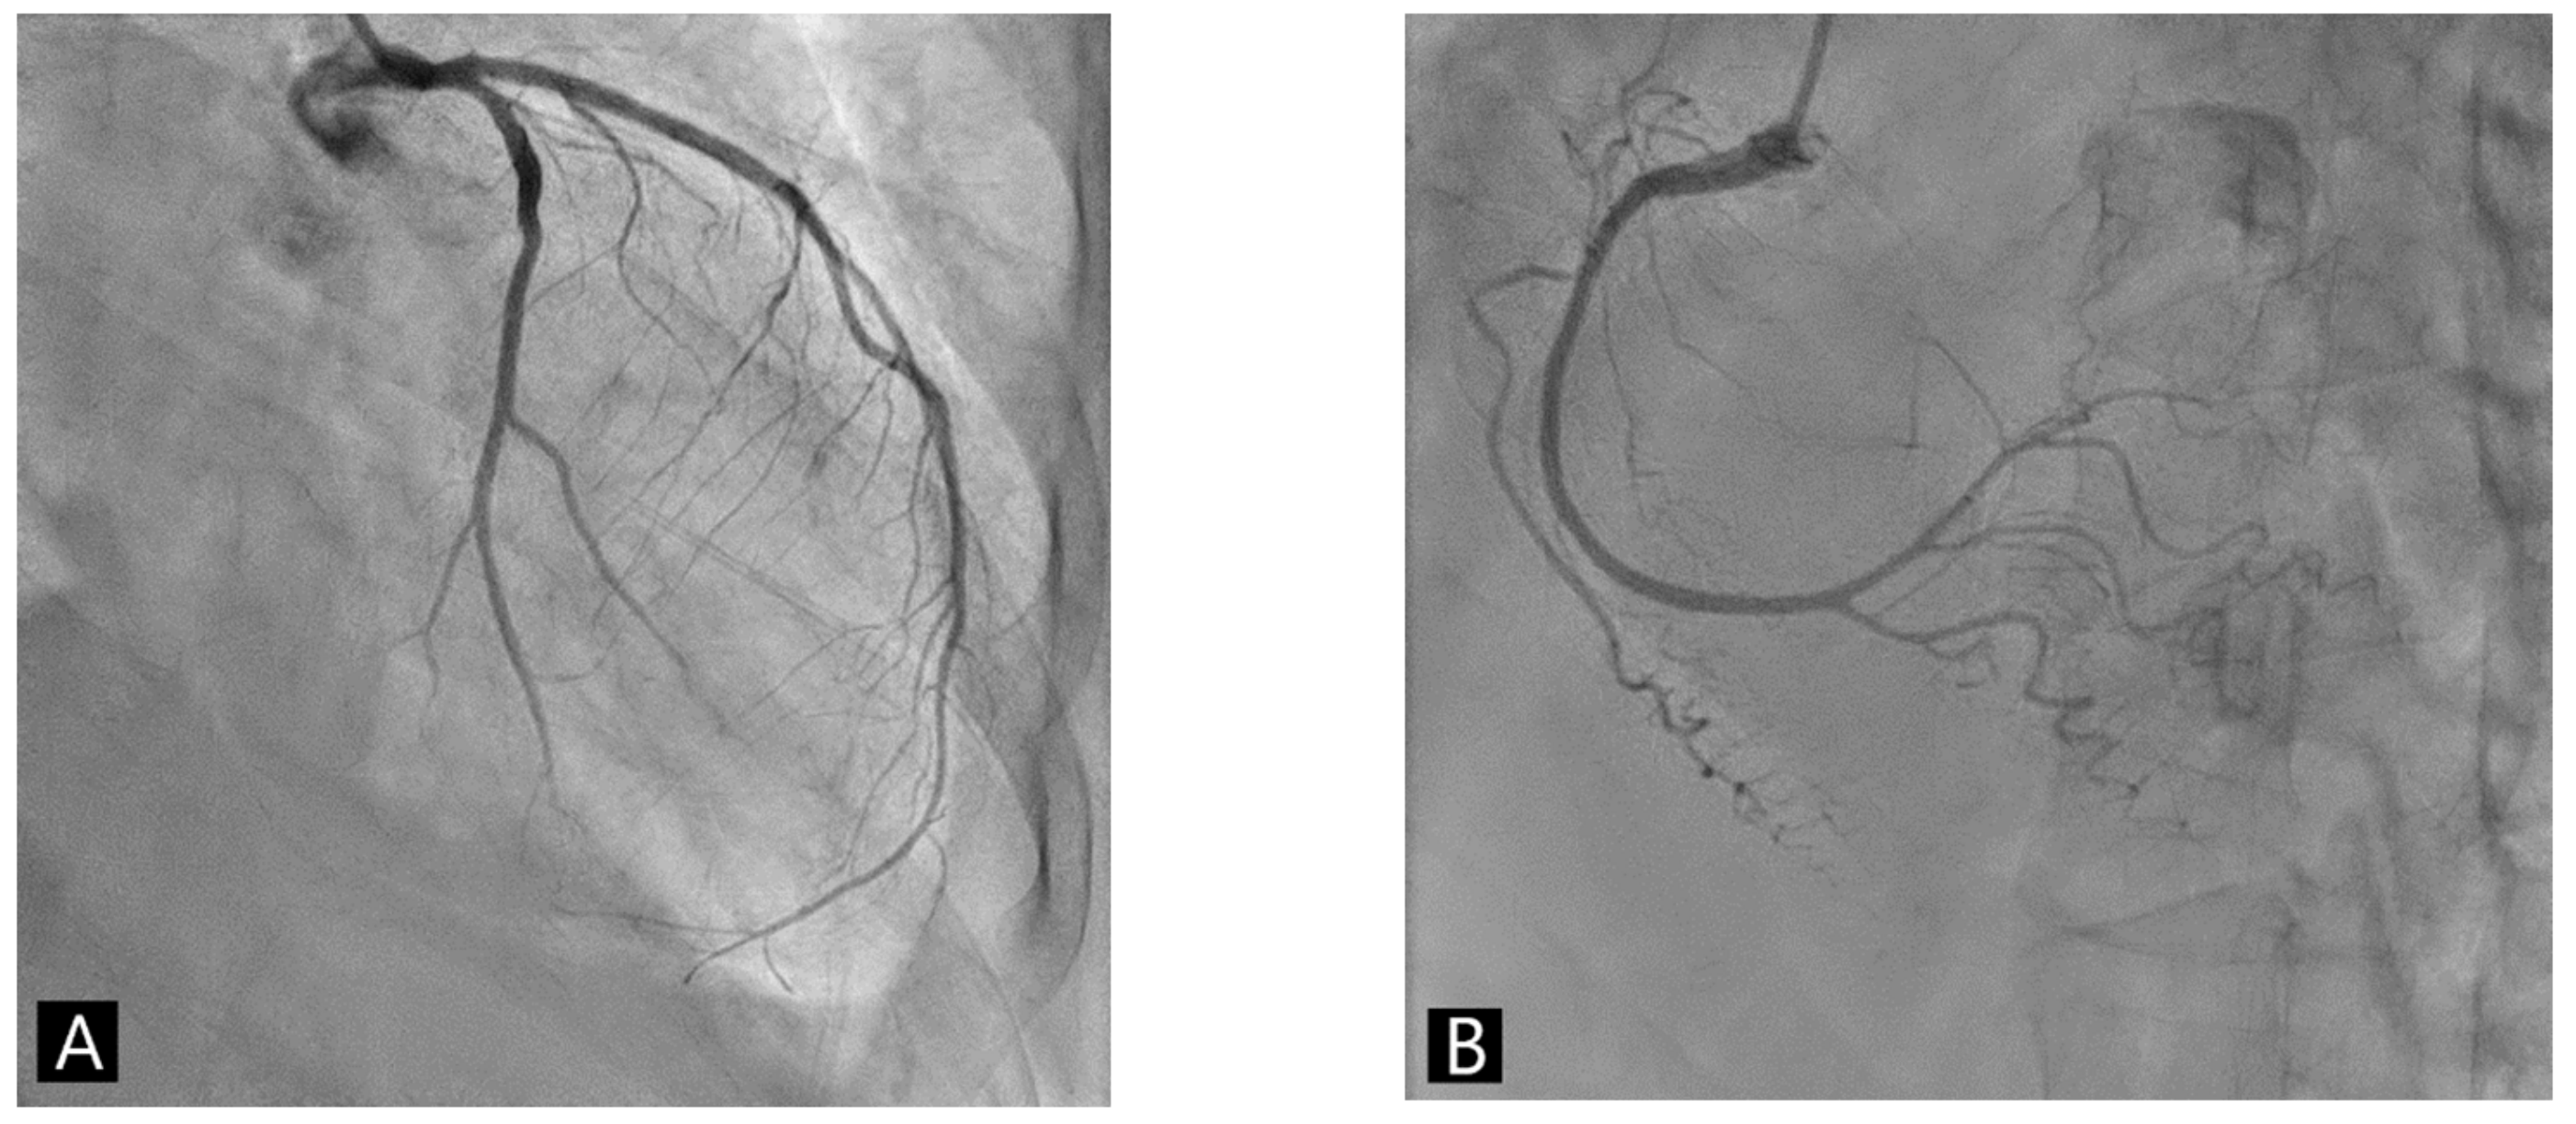

Echocardiography showed reduced left ventricular systolic function as an ejection fraction of 45% and akinesia of apex with preserved systolic wall motion in mid-ventricular and basal left ventricle of the heart (Figure 2A and Supplementary Video S1). Coronary angiography revealed the absence of obstructive coronary artery disease (Figure 3). The left ventriculography showed a typical feature with apical ballooning (Figure 2B and Supplementary Video S2).

We administered low-dose bisoprolol and diuretics. She also received carbimazole and steroids. On day 6, a follow-up ECG showed normal sinus rhythm. Repeat transthoracic echocardiography demonstrated the rapid recovery of apical ballooning of the left ventricle without any apical akinesia (Figure 2C and Supplementary Video S3). ECG tracings during echocardiography showed that the negative T wave recovered more slowly during the subacute phase. The transient abnormal left ventricular systolic function, transient ECG changes, and absence of obstructive coronary artery disease were suggestive of Takotsubo syndrome (TTS) and the patient was diagnosed with TTS. The patient was finally discharged with bisoprolol, propylthiouracil (200 mg daily), and prednisolone (5 mg daily).

Figure 2. Left ventriculogram and serial echocardiogram of Takotsubo syndrome occurring after COVID-19 mRNA vaccination. (A,B) Echocardiography (four-chamber images) and left ventriculography at the presentation of Takotsubo syndrome after COVID-19 mRNA vaccination. (C) Repeat echocardiography (four-chamber images) revealed an improvement in apical ballooning on day 6. Notice the slow recovery of the negative T wave during the subacute phase (left panel: end-diastolic phase, right panel: end-systolic phase).